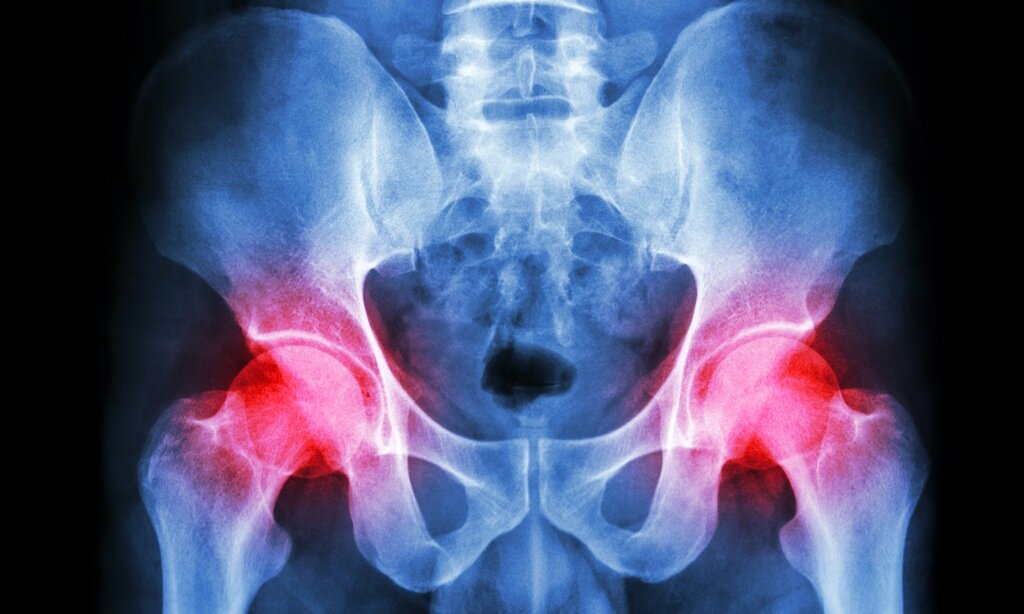

Коксартроз. Продолжение.

ЛЕЧЕНИЕ КОКСАРТРОЗА.

Какое лечение коксартроза ТБС будет проведено, зависит от стадии заболевания и степени поражения. Обязательно должен быть разработан комплекс лечебных мероприятий, направленных на: